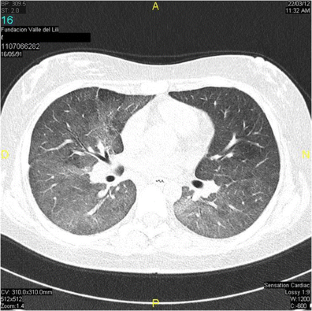

Fig. 2